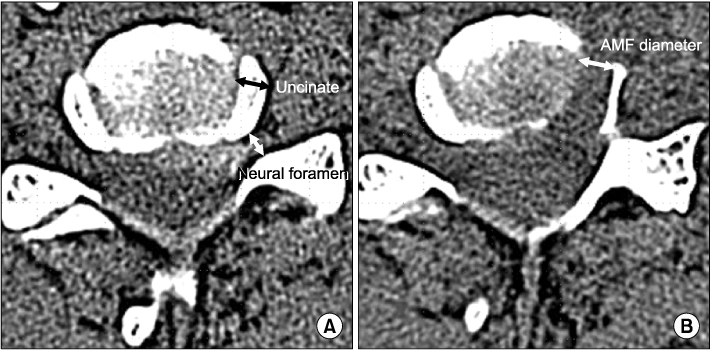

Fig. 2

(A) Diameter of the uncinate process is measured at the preoperative axial CT image showing the widest area of the disc. Diameter of the neural foramen was measured at the point just medial to the fossa locating the dorsal root ganglion. (B) Diameter of anterior microforaminotomy is measured on the postoperative axial CT image. AMF, anterior microforaminotomy.

Fig. 2 (A) Diameter of the uncinate process is measured at the preoperative axial CT image showing the widest area of the disc. Diameter of the neural foramen was measured at the point just medial to the fossa locating the dorsal root ganglion. (B) Diameter of anterior microforaminotomy is measured on the postoperative axial CT image. AMF, anterior microforaminotomy.